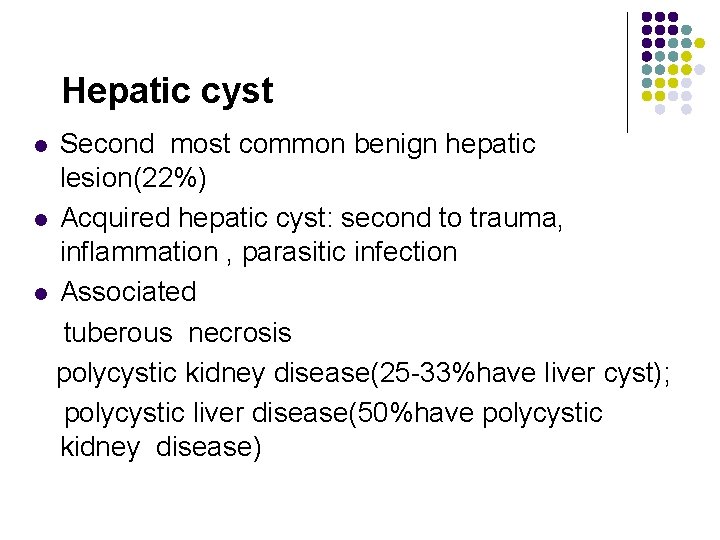

Pathology of the Live Focal Hepatic Disease l Cystic Lesions l Hepatic cysts may be congenital or acquired , solitary , or multiple. Patients are often asymptomatic, except patients who have large cysts , which can compress the hepatic vasculature or ductal system.

Pathology of the Live Focal Hepatic Disease l Cystic Lesions within the liver include the following : l Simple or congenital hepatic cysts l Traumatic cysts l Parasitic cysts l Inflammatory cysts l Polycystic disease l Pseudo-cysts

Hepatic cyst Second most common benign hepatic lesion(22%) l Acquired hepatic cyst: second to trauma, inflammation , parasitic infection l Associated tuberous necrosis polycystic kidney disease(25 -33%have liver cyst); polycystic liver disease(50%have polycystic kidney disease) l